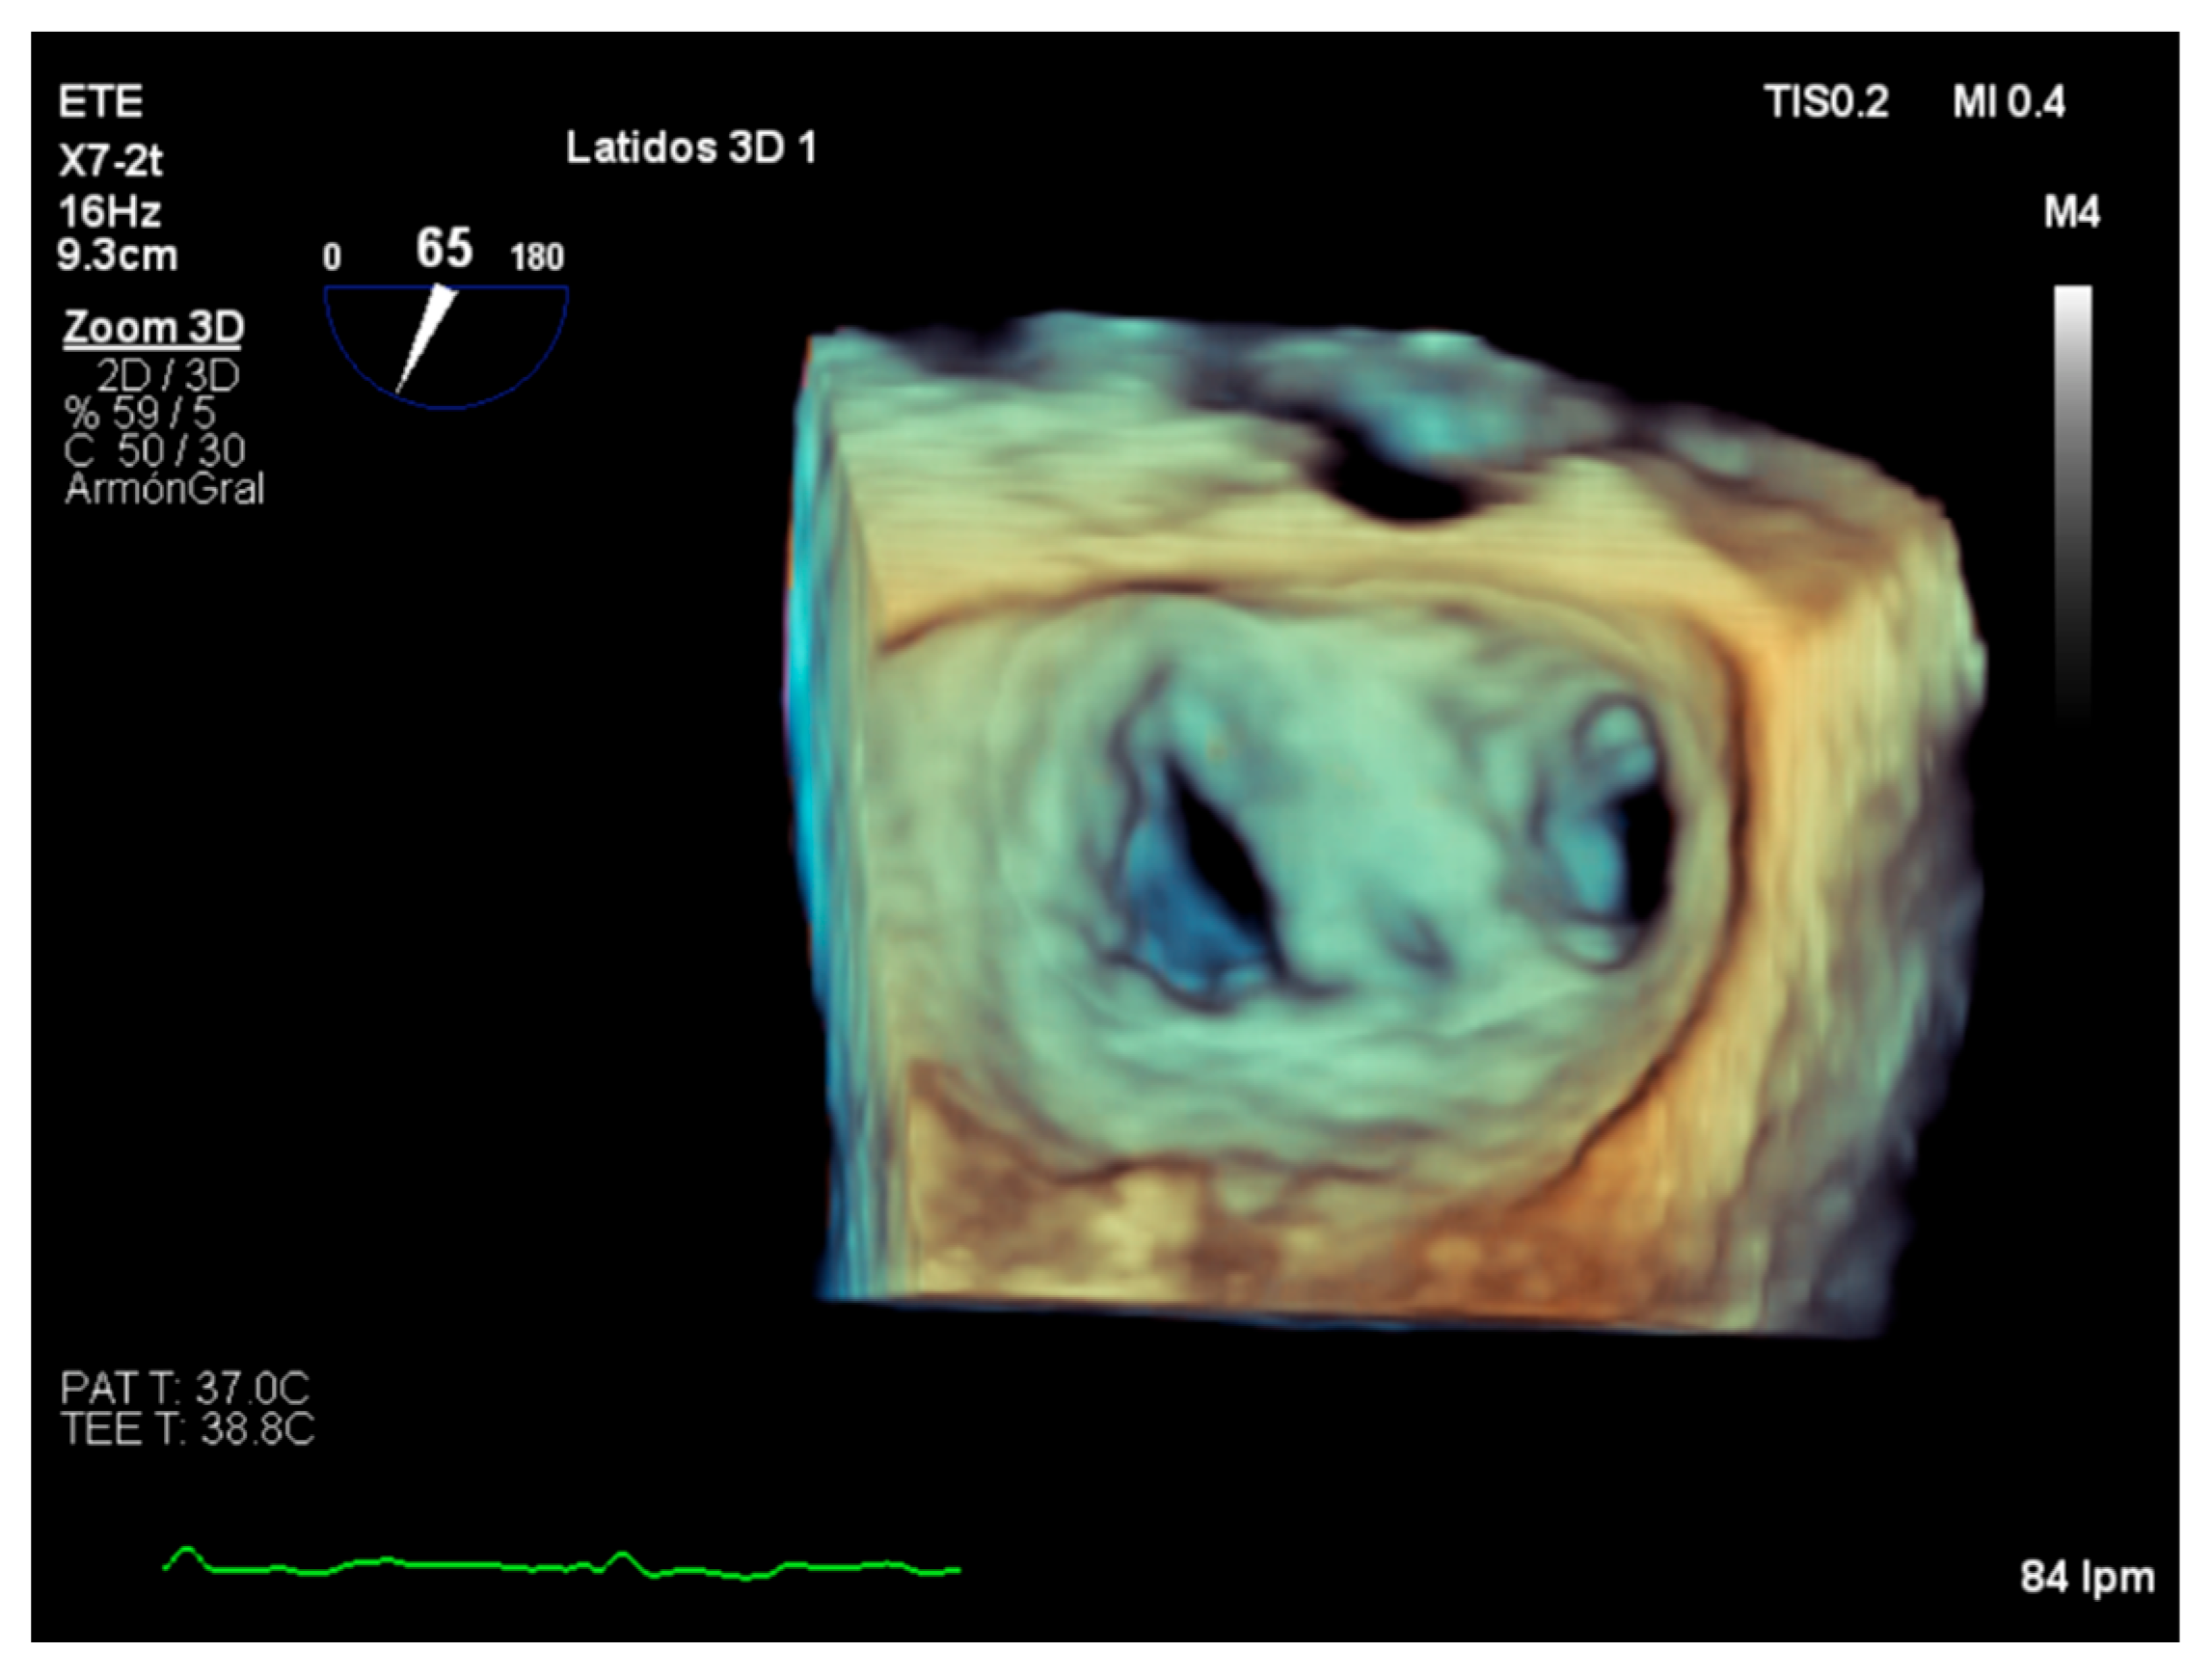

4. Assessment of Suitability of Valvular Repair